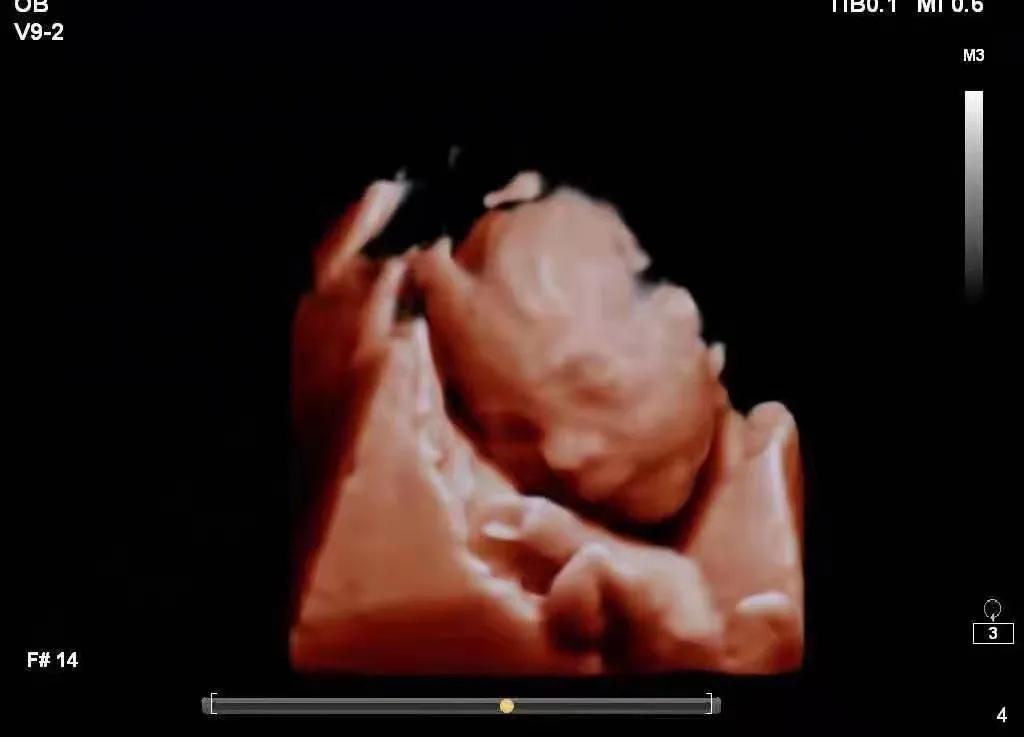

近日,深圳罗湖医院生殖科(原*警武**医院生殖中心)李颂军主任在微信上收到了患者Q女士发过来的宝宝的四维照片及检查报告,照片里的那个22周的小小人儿让人满怀期待,心生疼爱。

(22周的可爱萌宝)